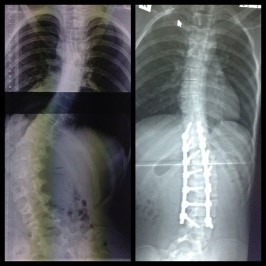

Josh’s before and after x-ray of his back after scoliosis surgery

During that time Josh was diagnosed with scoliosis. Many trips were had back and forth to Westmead to the scoliosis clinic to check Josh’s spine.

Josh continued to grow at a rapid rate and out grew his mum quick. He soon caught up to his Dad. This wasn’t in Josh’s favour, as his Scoliosis became quite bad and needed to be corrected.

In 2014 Josh underwent spinal fusion surgery to correct his spine. He now has 14 screws and 2 large rods in his back to keep him a bit straighter. He healed from the surgery without any complications and at that time he became even more of a hero to us. It was one of the bravest things we will ever witness.